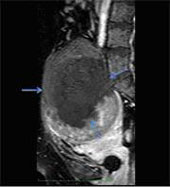

She had an intrauterine contraceptive device (IUCD), which was removed before the procedure. Ablation of the fibroid was carried out using High Intensity Focused Ultrasound under MRI guidance. The entire procedure lasted about 2 hours, after which intravenous gadolinium based contrast was administered a non-perfused volume of 75-80% was obtained (Fig. 2). The patient tolerated the procedure well.

Fig. 2 - Post Contrast Fat Saturated T1 weighted sagittal image showing a large internal area of non-perfusion (arrows), which is the ablated area.